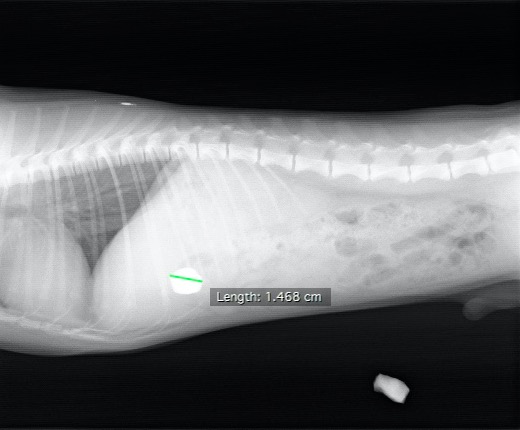

すぐにX線検査を行ったところ、胃内に石と思われる2㎝弱のX線不透過物が見つかりました。

横からのX線写真。白く写っているものが石と思われる異物です。参考のため、近くにあった石を一緒に写しています。